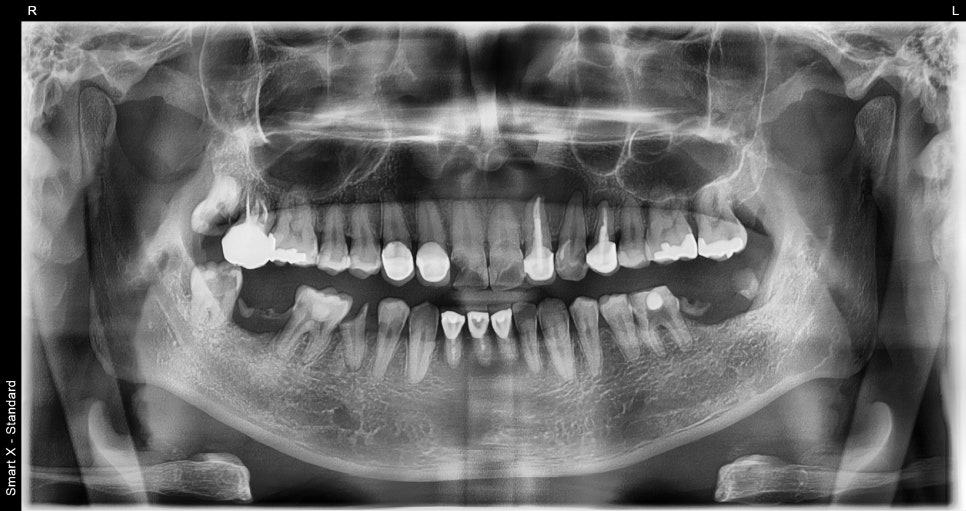

환자분은 외상으로 인해 앞니가 일부 깨진 상태로 내원하셨습니다.

겉보기에는 앞니 끝이 살짝 깨져 보이는 정도였지만,

정확한 진단을 위해 파노라마 X-ray와 CT 촬영을 진행했습니다.

단순한 파절로 보였던 앞니 내부를 확인해보니

#11번 치아 뿌리 부위에 큰 낭종(치근단낭종)이 형성되어 있었고,

전체적으로 치아가 부러지고 치료가 필요한 부분이 많았습니다.